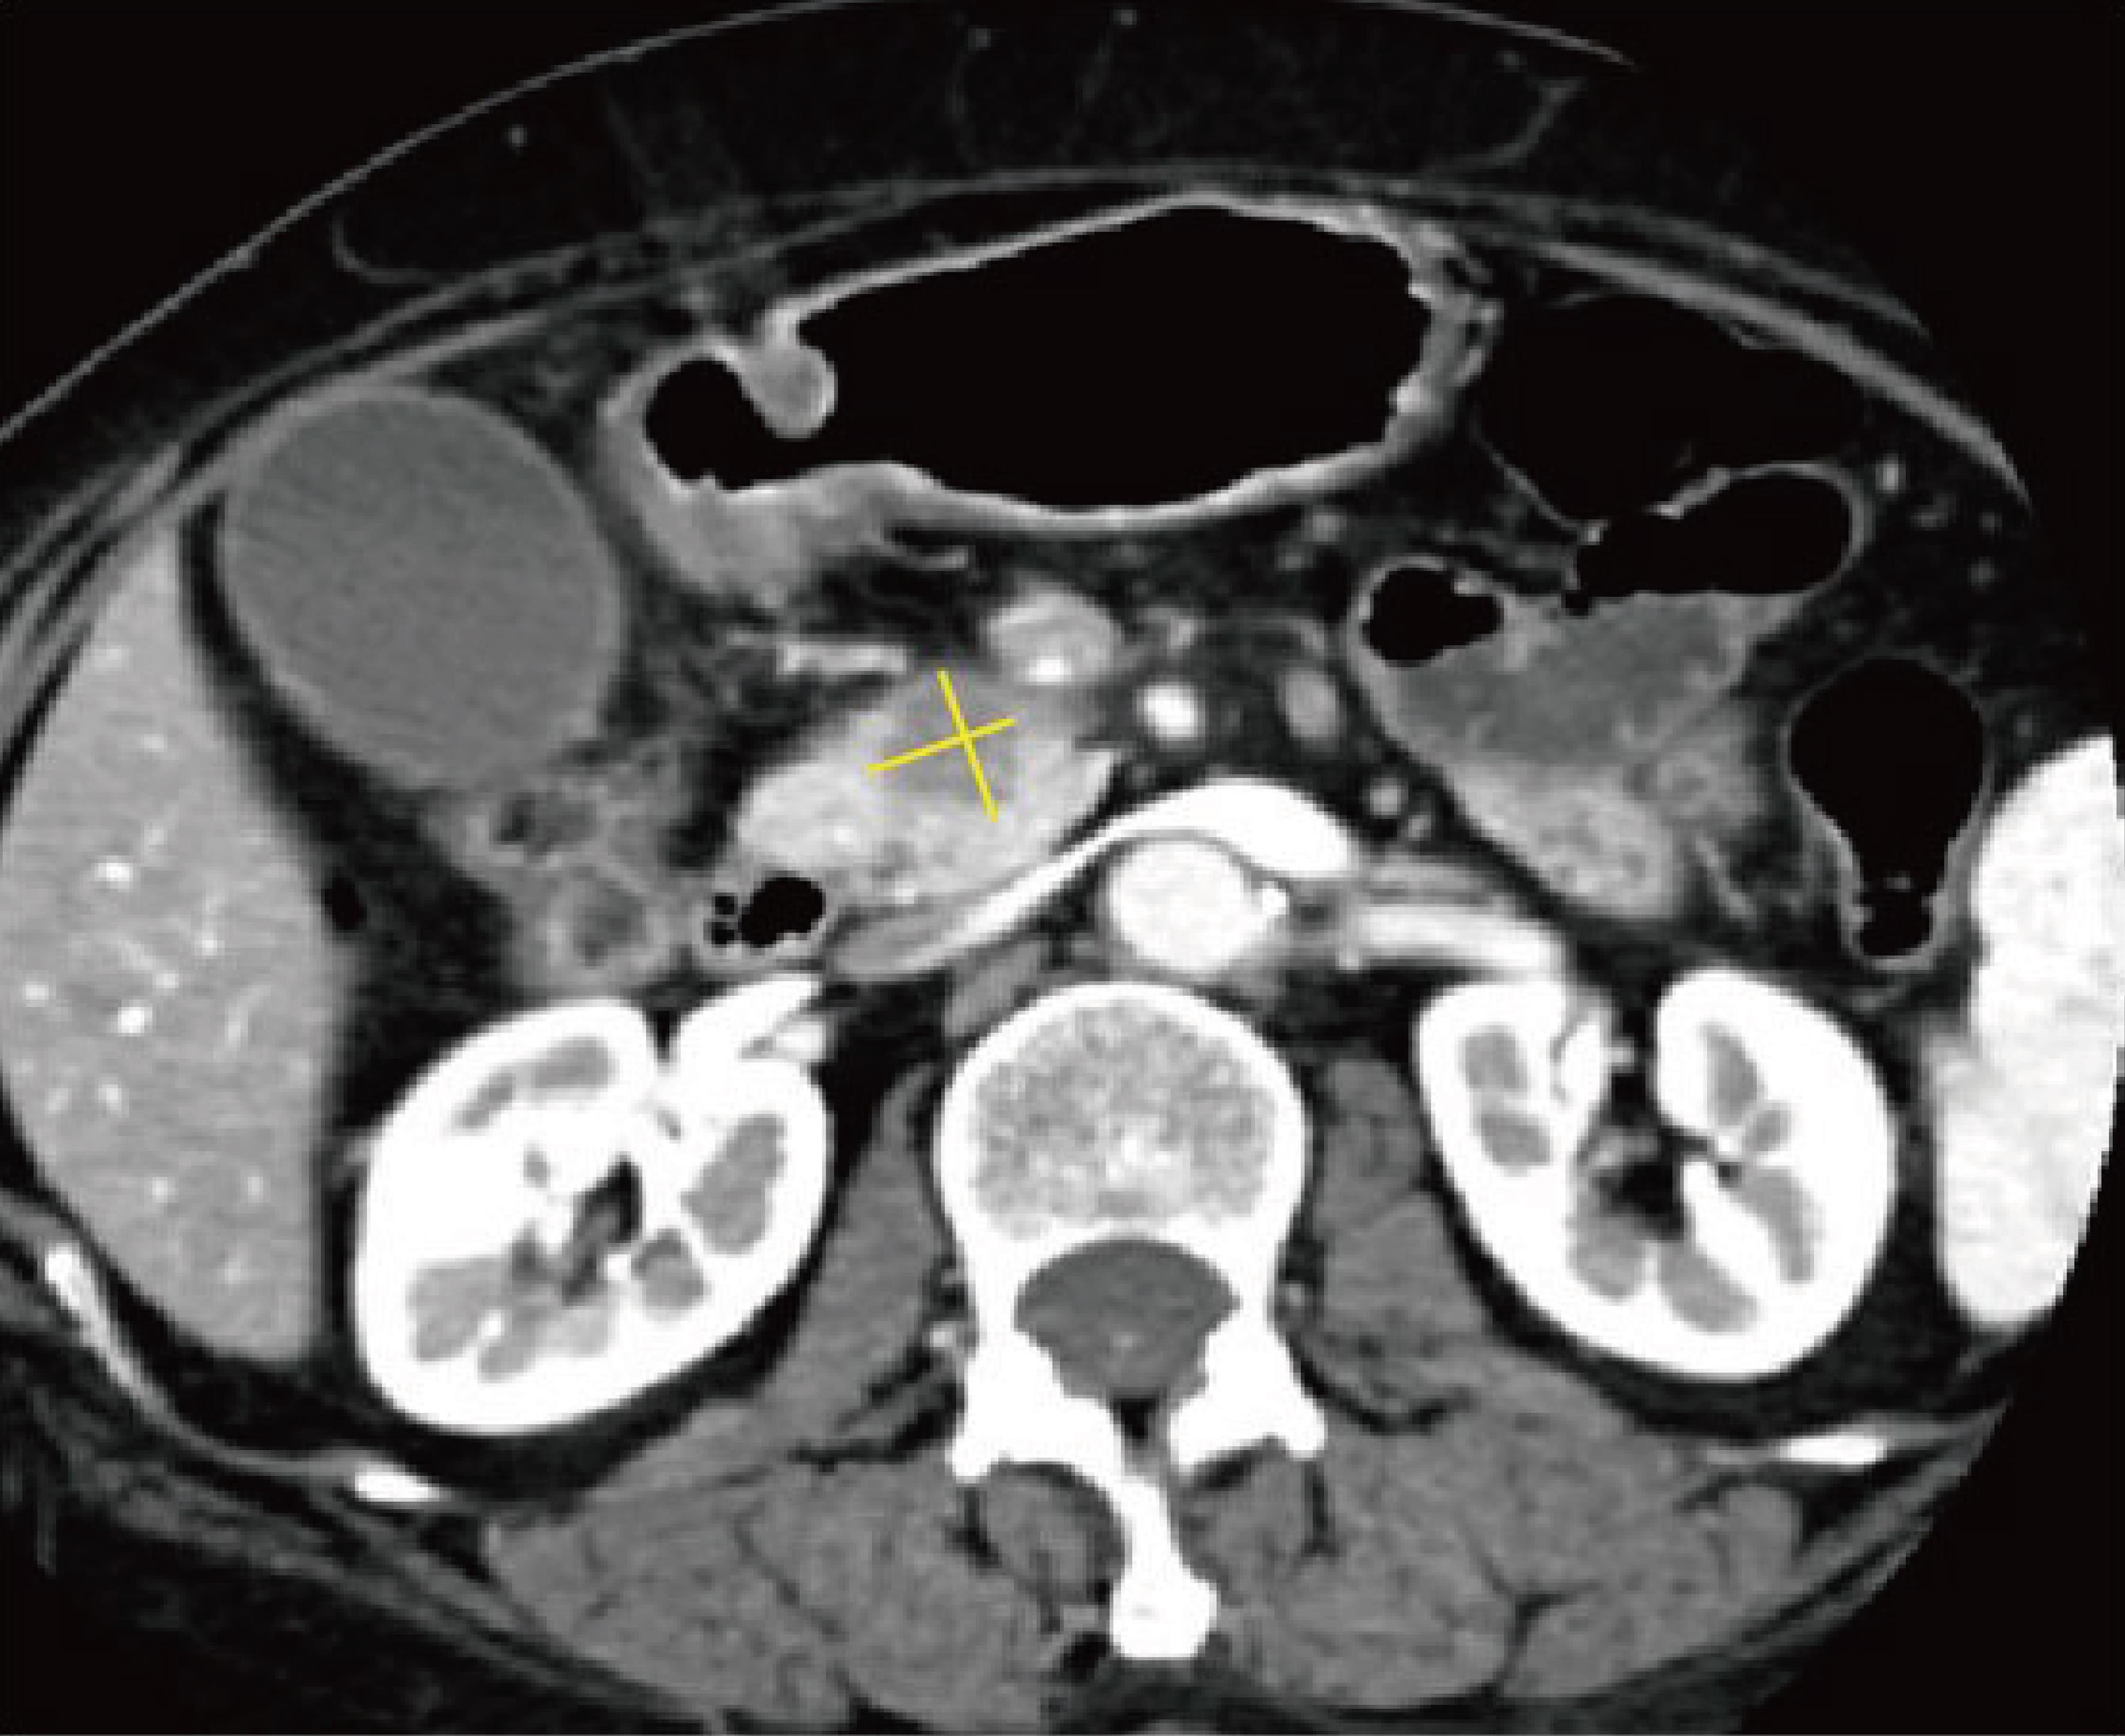

Is evaluation of pseudocysts/retention cysts necessary?

Recommendation 13: Evaluation for the presence of pseudocysts or retention cysts is necessary.

Evidence quality: B; Recommendation strength: Strong

Explanation: Pancreatic cancer originates from ductal epithelial cells and can obstruct the pancreatic duct, causing upstream retention of pancreatic juice and cystic dilation, forming retention cysts lined by ductal epithelium on pathology.101 When intraductal pressure increases or the pancreatic duct ruptures, pseudocysts may form; these can also develop secondary to obstructive acute pancreatitis. Pseudocysts consist of fluid collections surrounded by non-epithelial tissue within or adjacent to the pancreas.102 Differentiation between retention cysts and pseudocysts requires pathological examination; radiologically, they are often difficult to distinguish, both typically presenting as unilocular cysts with variably thick walls, commonly located in the pancreatic body or tail without obvious mural nodules.101 Studies have identified pancreatic cysts ≥5 mm as independent predictors for pancreatic cancer development.103 In patients with elevated CA19-9 and retention cysts, vigilance for small or isoattenuating pancreatic cancers nearby is warranted.50,104 This guideline recommends that when retention or pseudocysts are detected, they should be clearly reported with measurements of size and description of location (Fig. 6).

Pseudocyst formation secondary to pancreatic cancer.

Fig. 6  Pseudocyst formation secondary to pancreatic cancer.

Axial arterial-phase computed tomography (CT) image demonstrates a hypodense mass in the pancreatic body (white arrow) and an adjacent lower-attenuation lesion (yellow arrow) representing a pseudocyst. The measurement method is illustrated by the yellow line.